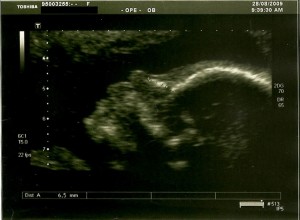

Ecografia 20 Semanas e 5 dias

Hoje fizemos a ecografia morfológica.

Foram analisadas todas as partes do corpo da nossa bebé, desde o cérebro até aos dedos, passando pelo nariz, lábios e orelhas, coração, estômago, rins e bexiga. Foi muito tranquilizador ver tudo com pormenor e perceber que aparentemente é tudo normal!